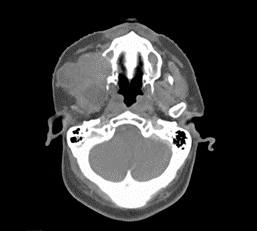

A cervicofacial contrast CT scan of the mandible revealed a tumor process involving the right hemiface (Figure 2), responsible for horizontal and vertical branch lysis as well as temporomandibular joint and lysis of the external edge of the right maxillary sinus (Figure 3), with retro-orbital extension measuring 12x8x6,5 cm compatible with tumor recurrence. Although biopsy shows ameloblastoma with follicular type.

Figure 2. CT showing swelling in the right mandibular region deforming the right hemiface

Figure 3. CT showing the tumor process leading to lysis of the external edge of the right maxillary sinus